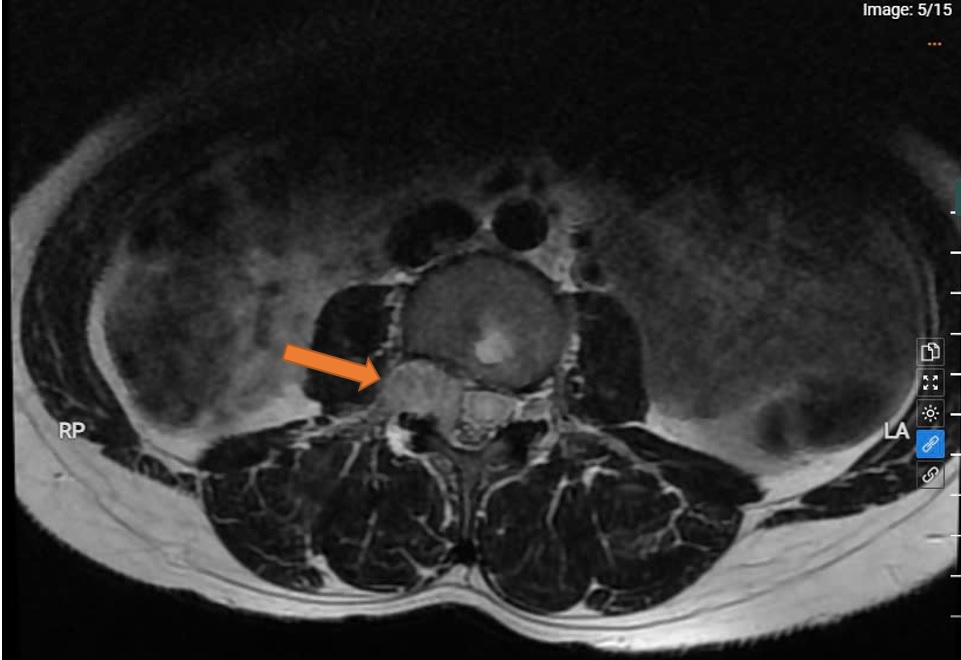

PHẪU THUẬT THÀNH CÔNG KHỐI U TỦY SỐNG CHÈN ÉP TỦY – GIÀNH LẠI CUỘC SỐNG CHO BỆNH NHÂN NỮ TRẺ TUỔI

16/04/2025Ngày 14/4/2025, khoa Phẫu thuật Thần kinh – Lồng ngực, Bệnh viện Đa khoa tỉnh Bắc Ninh đã phẫu thuật thành công khối u tuỷ sống thắt lưng lớn, chèn ép tủy nhiều, cho bệnh nhân Nguyễn Thị C sinh năm 1984. Ca mổ phức tạp kéo dài 3 giờ đồng hồ, với sự phối hợp chặt chẽ của ê-kíp phẫu thuật, đã bóc tách cắt thành công hoàn toàn khối u, bảo tồn nguyên vẹn các rễ thần kinh và tủy sống, giúp bệnh nhân thoát khỏi nguy cơ bại liệt, hồi phục tốt sau mổ.